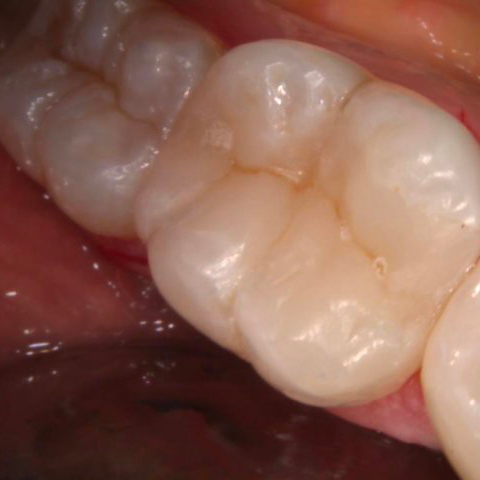

PROTHESES DENTAIRES

Si la structure de la dent n’est pas restaurable, il est nécessaire de créer un remplacement esthétique et fonctionnel qui s’intègrera harmonieusement dans la bouche sans y laisser voir le travail du médecin-dentiste.